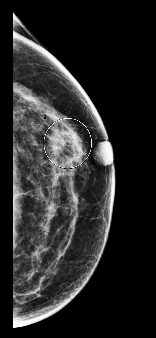

Lors du dépistage, deux masses ont été trouvées, l’une sur le sein droit (2cm DTN) et l’autre sur le sein gauche (A1 cm DTN), catégorisée comme suspecte.

La patiente a été rappelée pour une échographie. La biopsie réalisée a montré un cancer lobulaire infiltrant sur le sein gauche (deux masses).

MammoScreen détecte l’une des masses suspectes sur le sein gauche en score 8 sur la tomosynthèse.